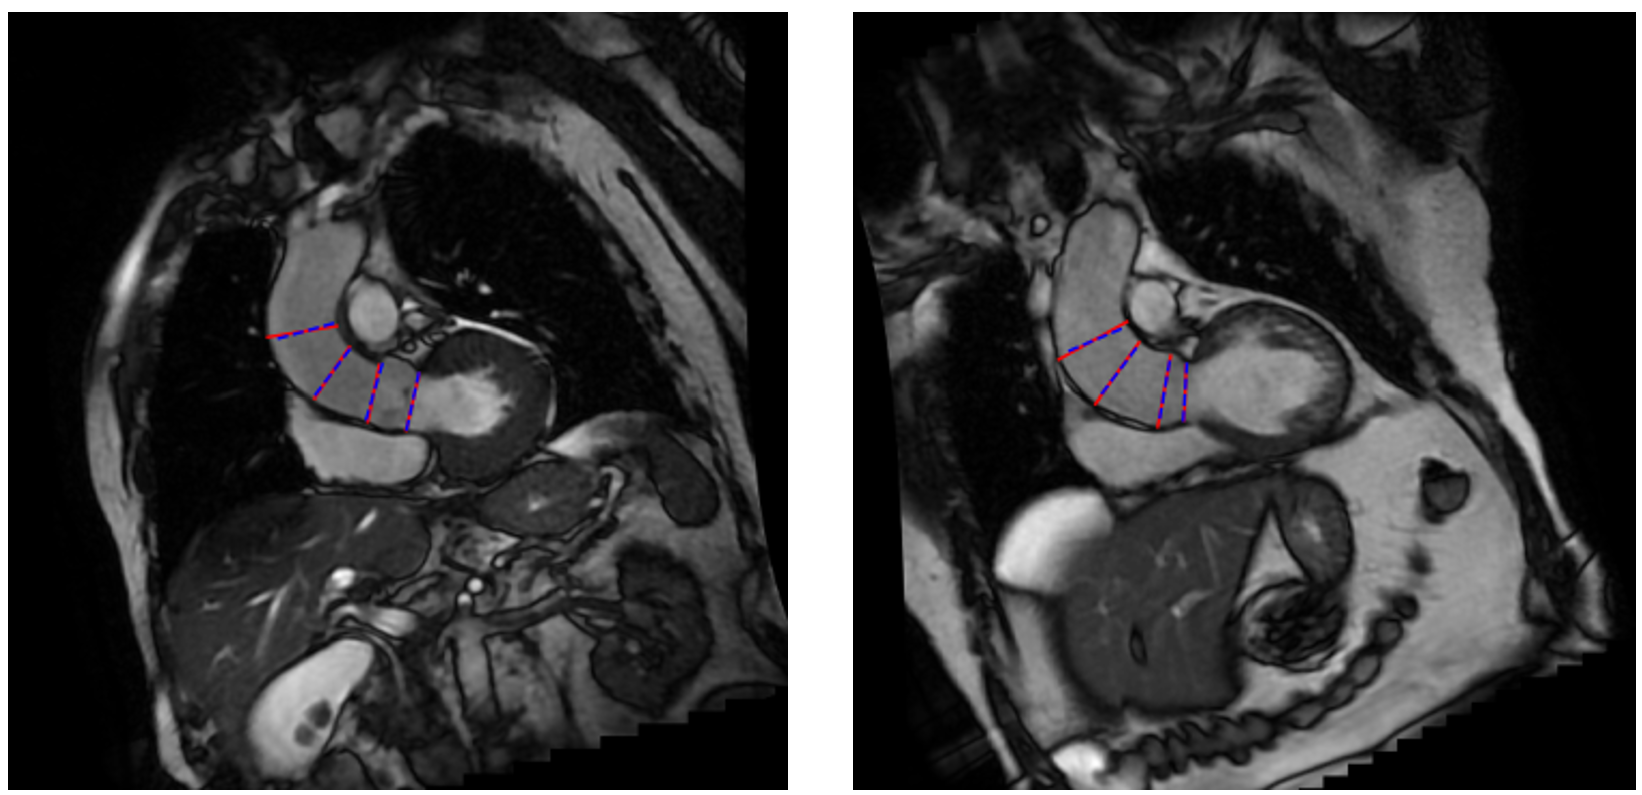

Figure 2: Box-whisker plots of the centerline distance and the flow measurement view angle discrepancy with respect to the four ground truth landmarks defined by the cardiologist.